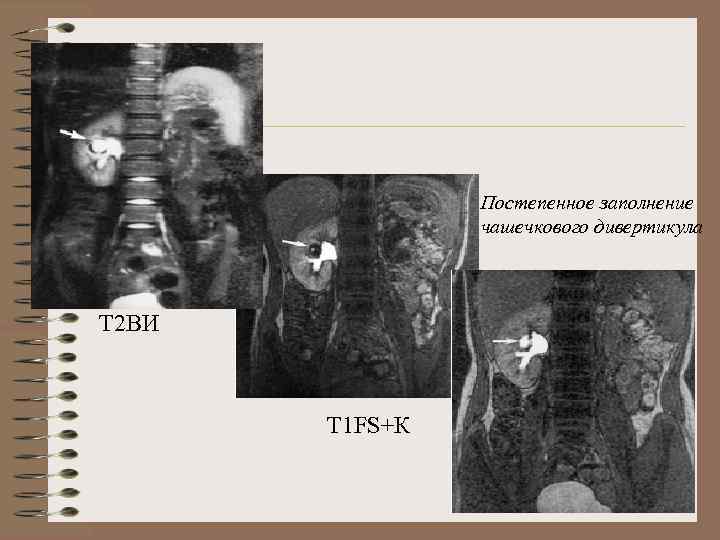

Постепенное заполнение чашечкового дивертикула Т 2 ВИ Т 1 FS+К